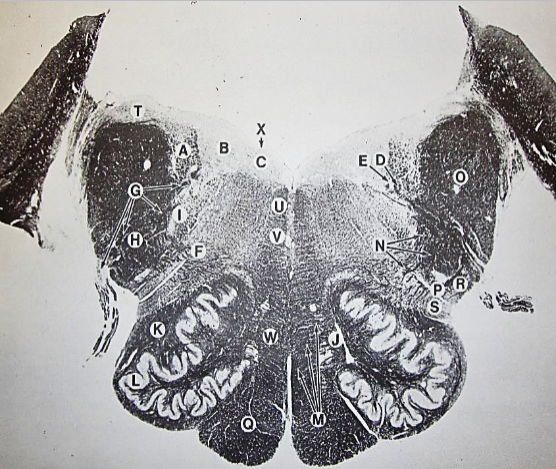

A

Fasciculus gracilis

B

gracile nucleus

C

fasciculus cuneatus

D

cuneate nucleus

E

spinal trigeminal tract

F+G collectively

spinal trigeminal nucleus

H

accessory nucleus

I

pyramidal decussation

J

rubrospinal tract

K

posterior spinocerebellar tract

L

anterior spinocerebellar tract

M

lateral spinothalamic tract

N

anterior spinothalamic tract

O

lateral vestibulospinal tract

P

medial longitudinal fasciculus

Q

tectospinal tract